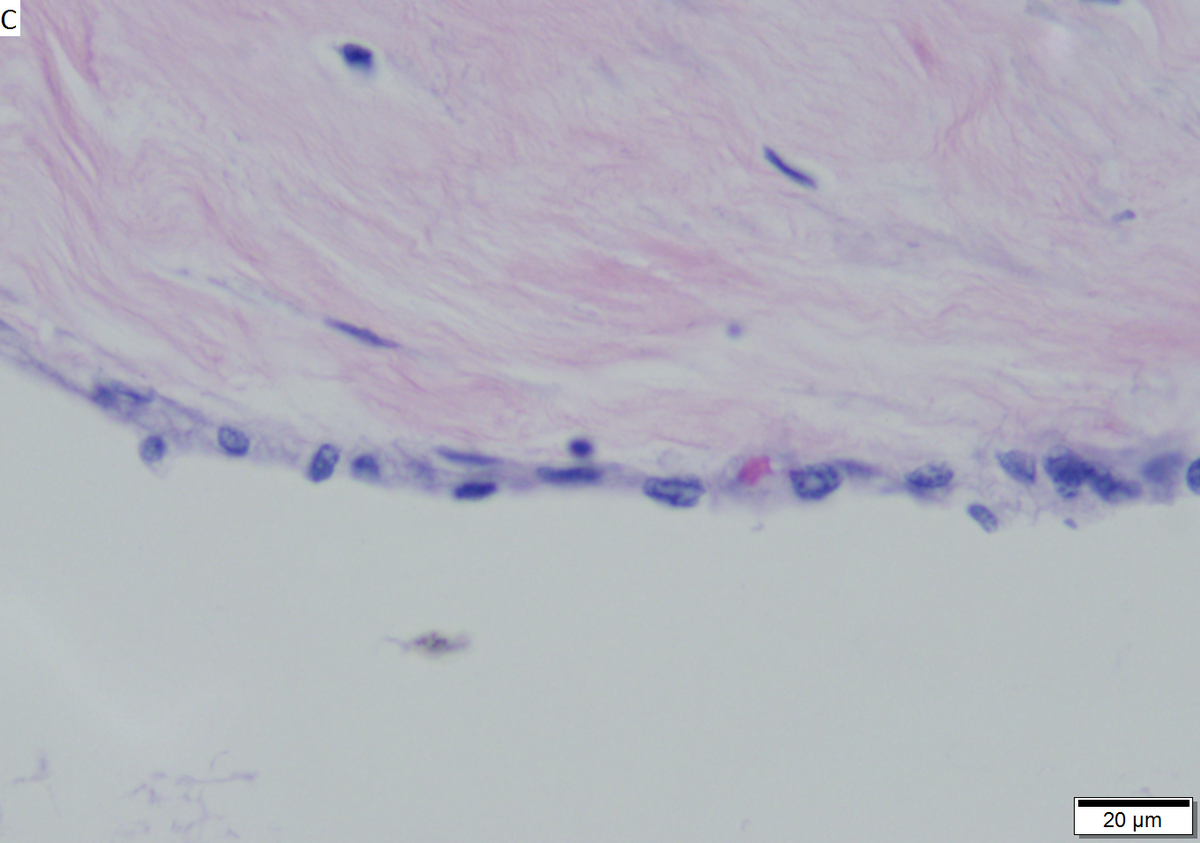

Microcystic serous cystadenoma of pancreas in a 62 year old woman. A. The tumor showed a central scar with multiple minute cysts; slight pressure yielded clear fluid. B. The mass comprises microcysts numberless. C. Cysts bear single cell linings with bland, amitotic nuclei. D. PAS without diastase shows positive cytoplasmic material. E. PAS with diastase shows the cytoplasmic material has been digested away. F. Keratin shows positive staining lining cells.

Stains

• PAS +ve.

• PASD -ve.

Stains PAS +ve, PASD -ve